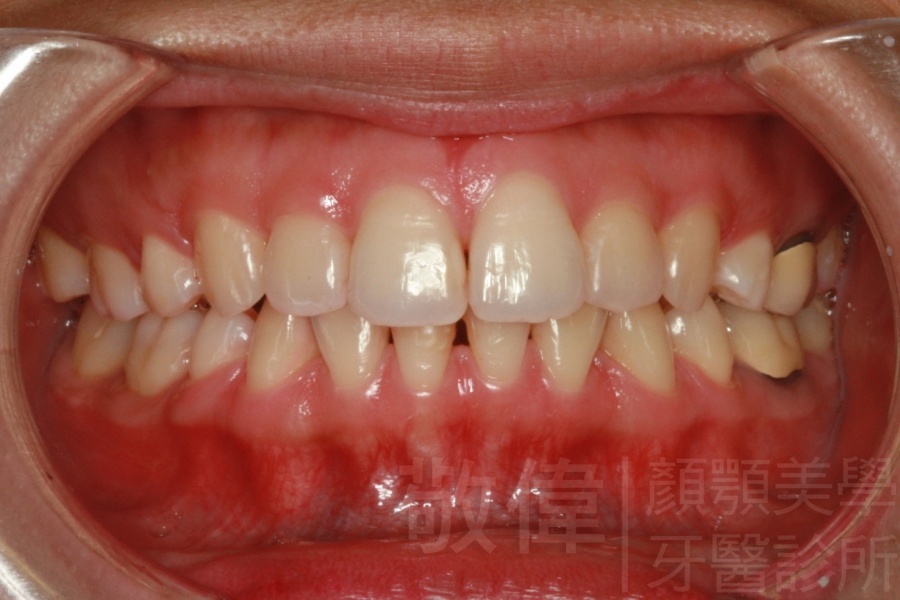

矯正前-上   矯正前-下

矯正後-上   矯正後-下

上下暴牙嘴唇不容易合起來,經矯正完成後,嘴唇很容易合起來。在學生時期的時候的他,舉止之間充滿著有自信,當時還參加了舞蹈社團,充滿了多采多姿的生活。